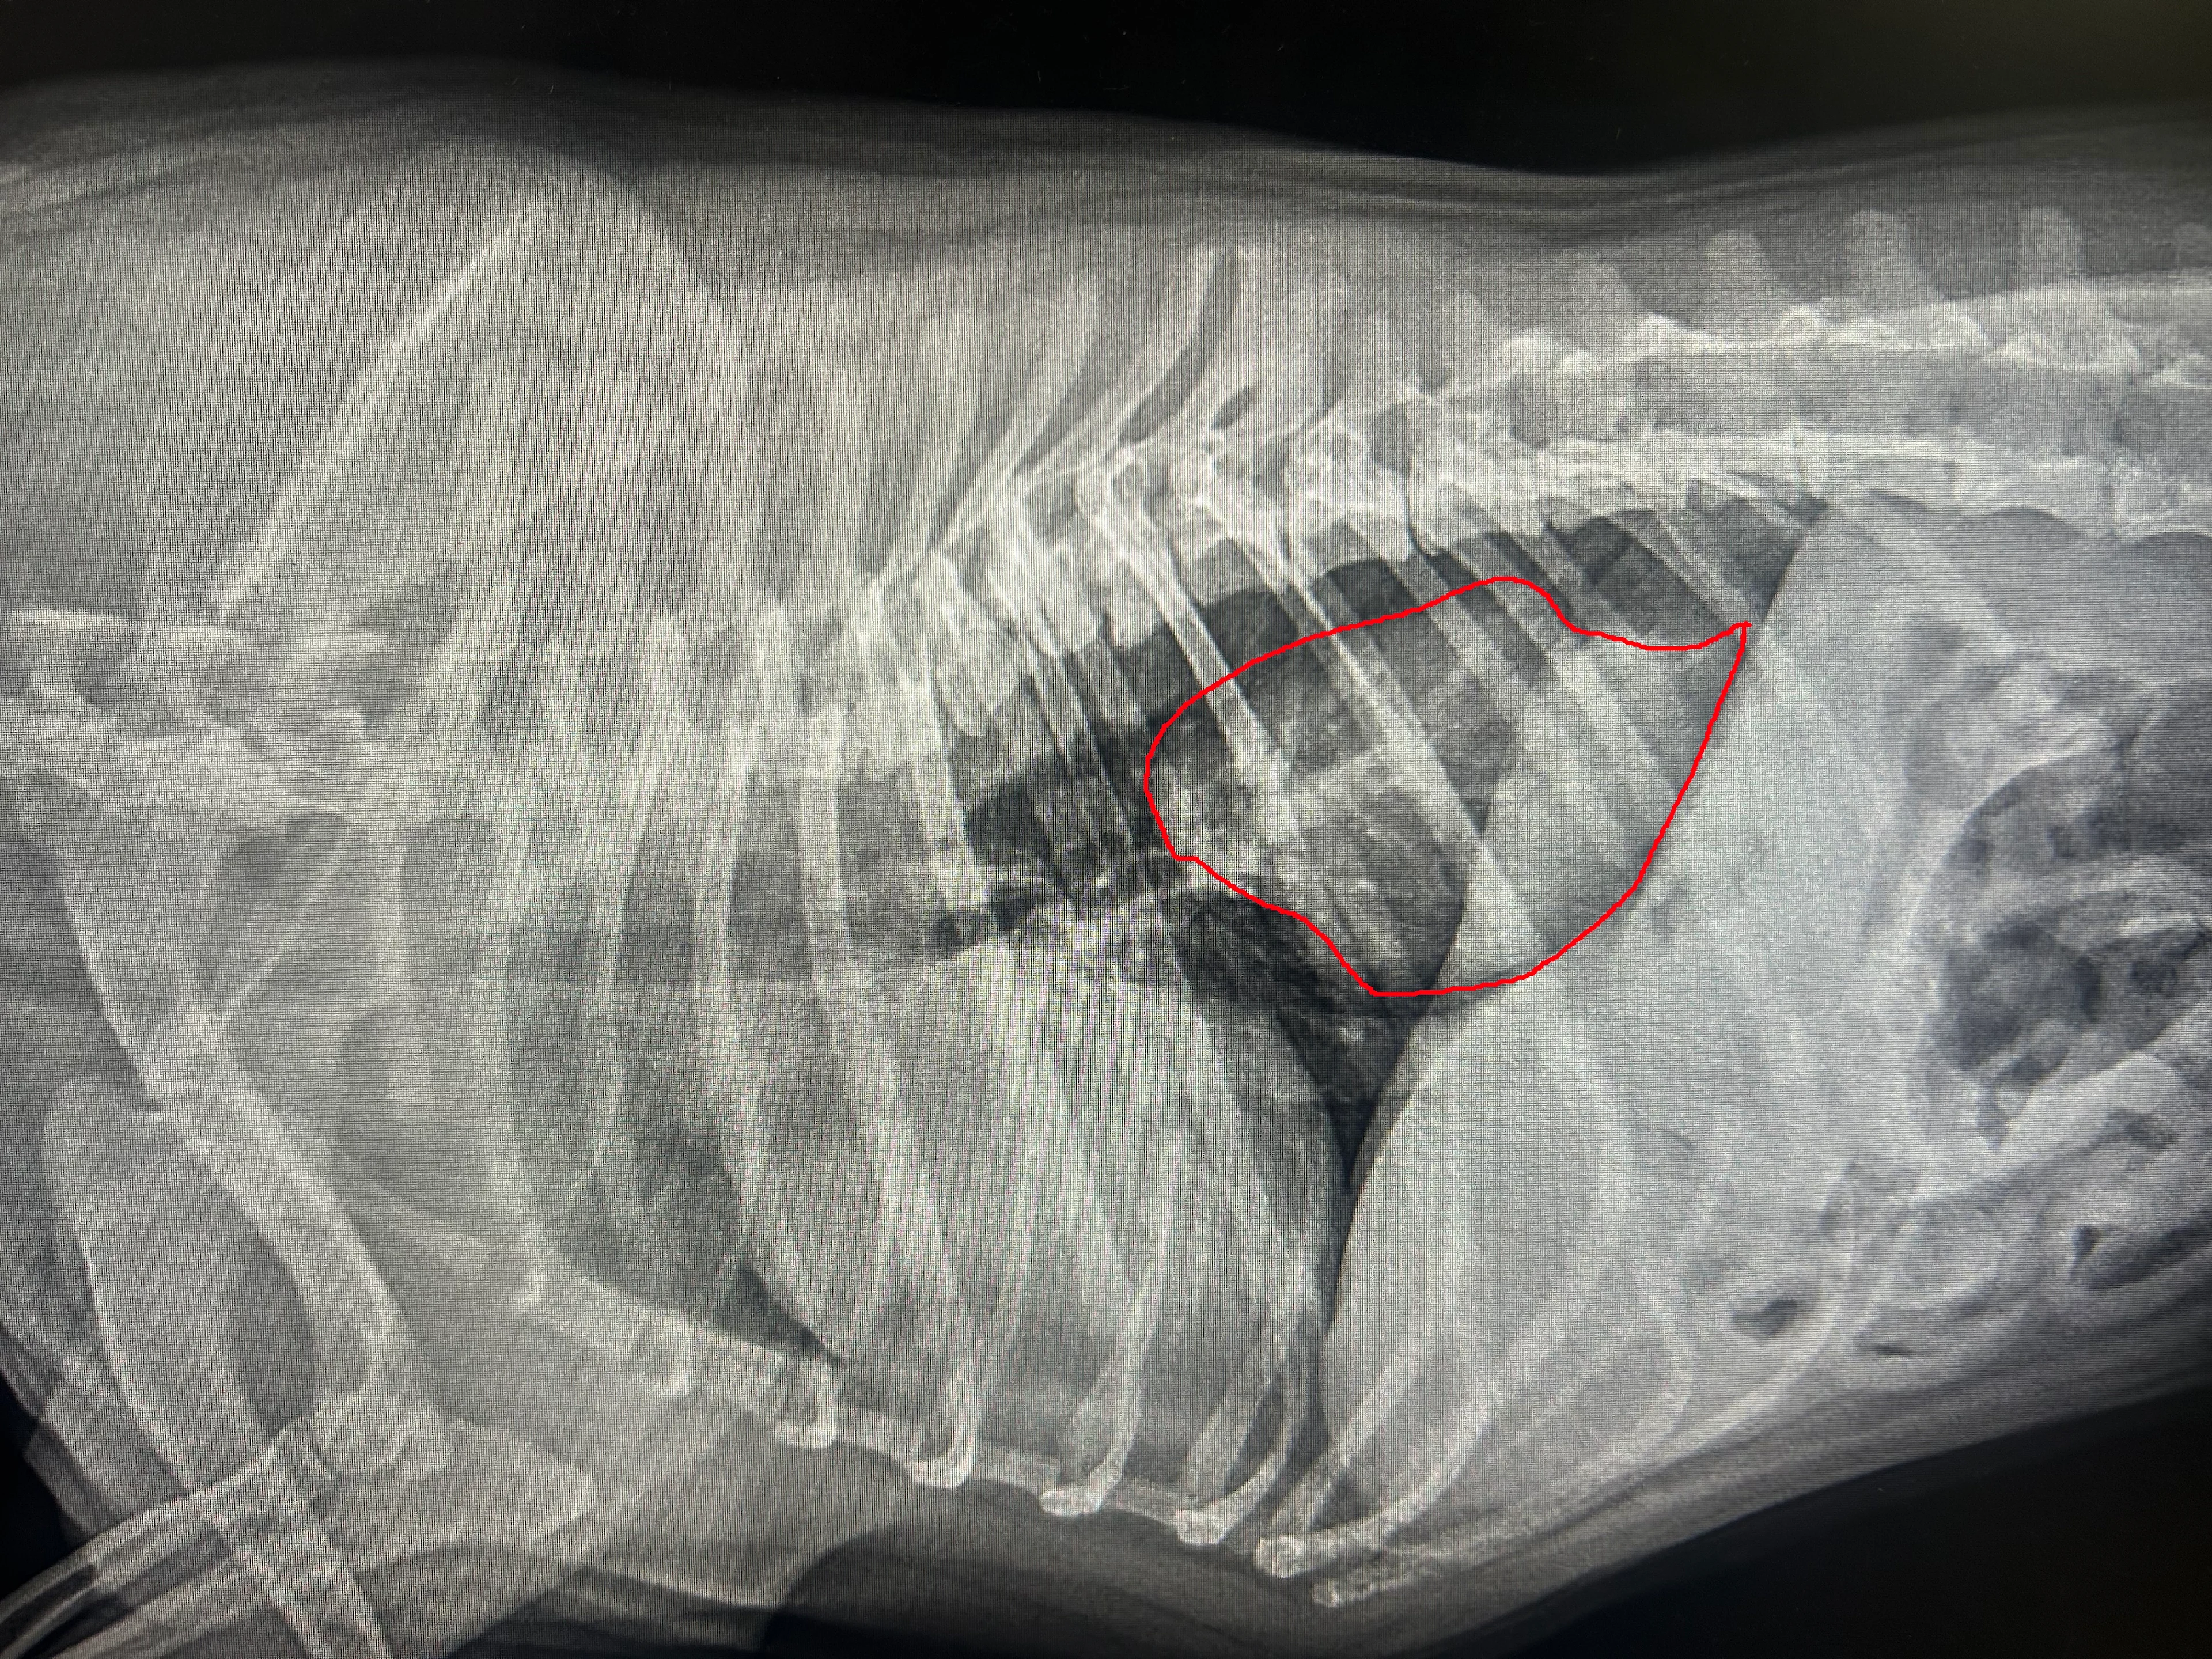

Lateral thoracic radiography was performed on a 3-year-old French bulldog with a history of multiple episodes of daily vomiting or regurgitation. Radiographs revealed a hiatal hernia (ie, movement of the stomach into the chest cavity; Figure).

FIGURE Hiatal hernia seen in a French bulldog

Hiatal hernias may be mistaken for masses or esophageal foreign bodies. These hernias are common in dogs with brachycephalic obstructive airway syndrome (BOAS) and thought to develop as a result of excessive negative intrathoracic pressure associated with increased upper airway resistance from airway disease. The narrowed upper airway makes breathing more difficult, leading to movement of the stomach through the esophageal hiatus in the diaphragm into the chest.